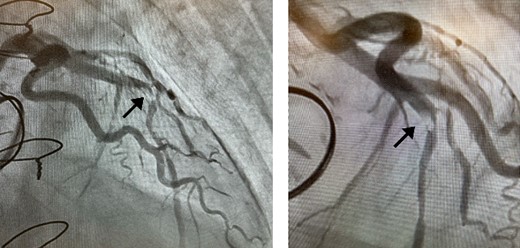

Postoperatively, an electrocardiogram revealed anterior ST-segment elevation, indicative of myocardial ischaemia. The patient then developed renal insufficiency. Given his haemodynamic stability, he was initially managed using coronary dilators and heparin. To improve renal function, coronary angiography was performed on the 10th postoperative day, which revealed a filling defect and 90% stenosis in the LAD artery (Fig. 1). Computed tomography (CT) revealed a high-density mass in the LAD artery with a mean CT value of 400 Hounsfield units (HUs) (Fig. 2). These findings indicated embolism, possibly due to a pledget from a previous surgery. A transcatheter approach was employed to remove the embolus, which was successfully extracted using a snare (Fig. 3a). Angiographic assessment revealed that the previously stenotic LAD demonstrated full perfusion, consistent with a thrombolysis in myocardial infarction (TIMI) flow grade of 3 (Fig. 3b). The patient recovered from catheterization without complications.

(a) The pledget was removed by transcatheter; (b) TIMI Grade 3 flow in the LAD artery after percutaneous coronary intervention.